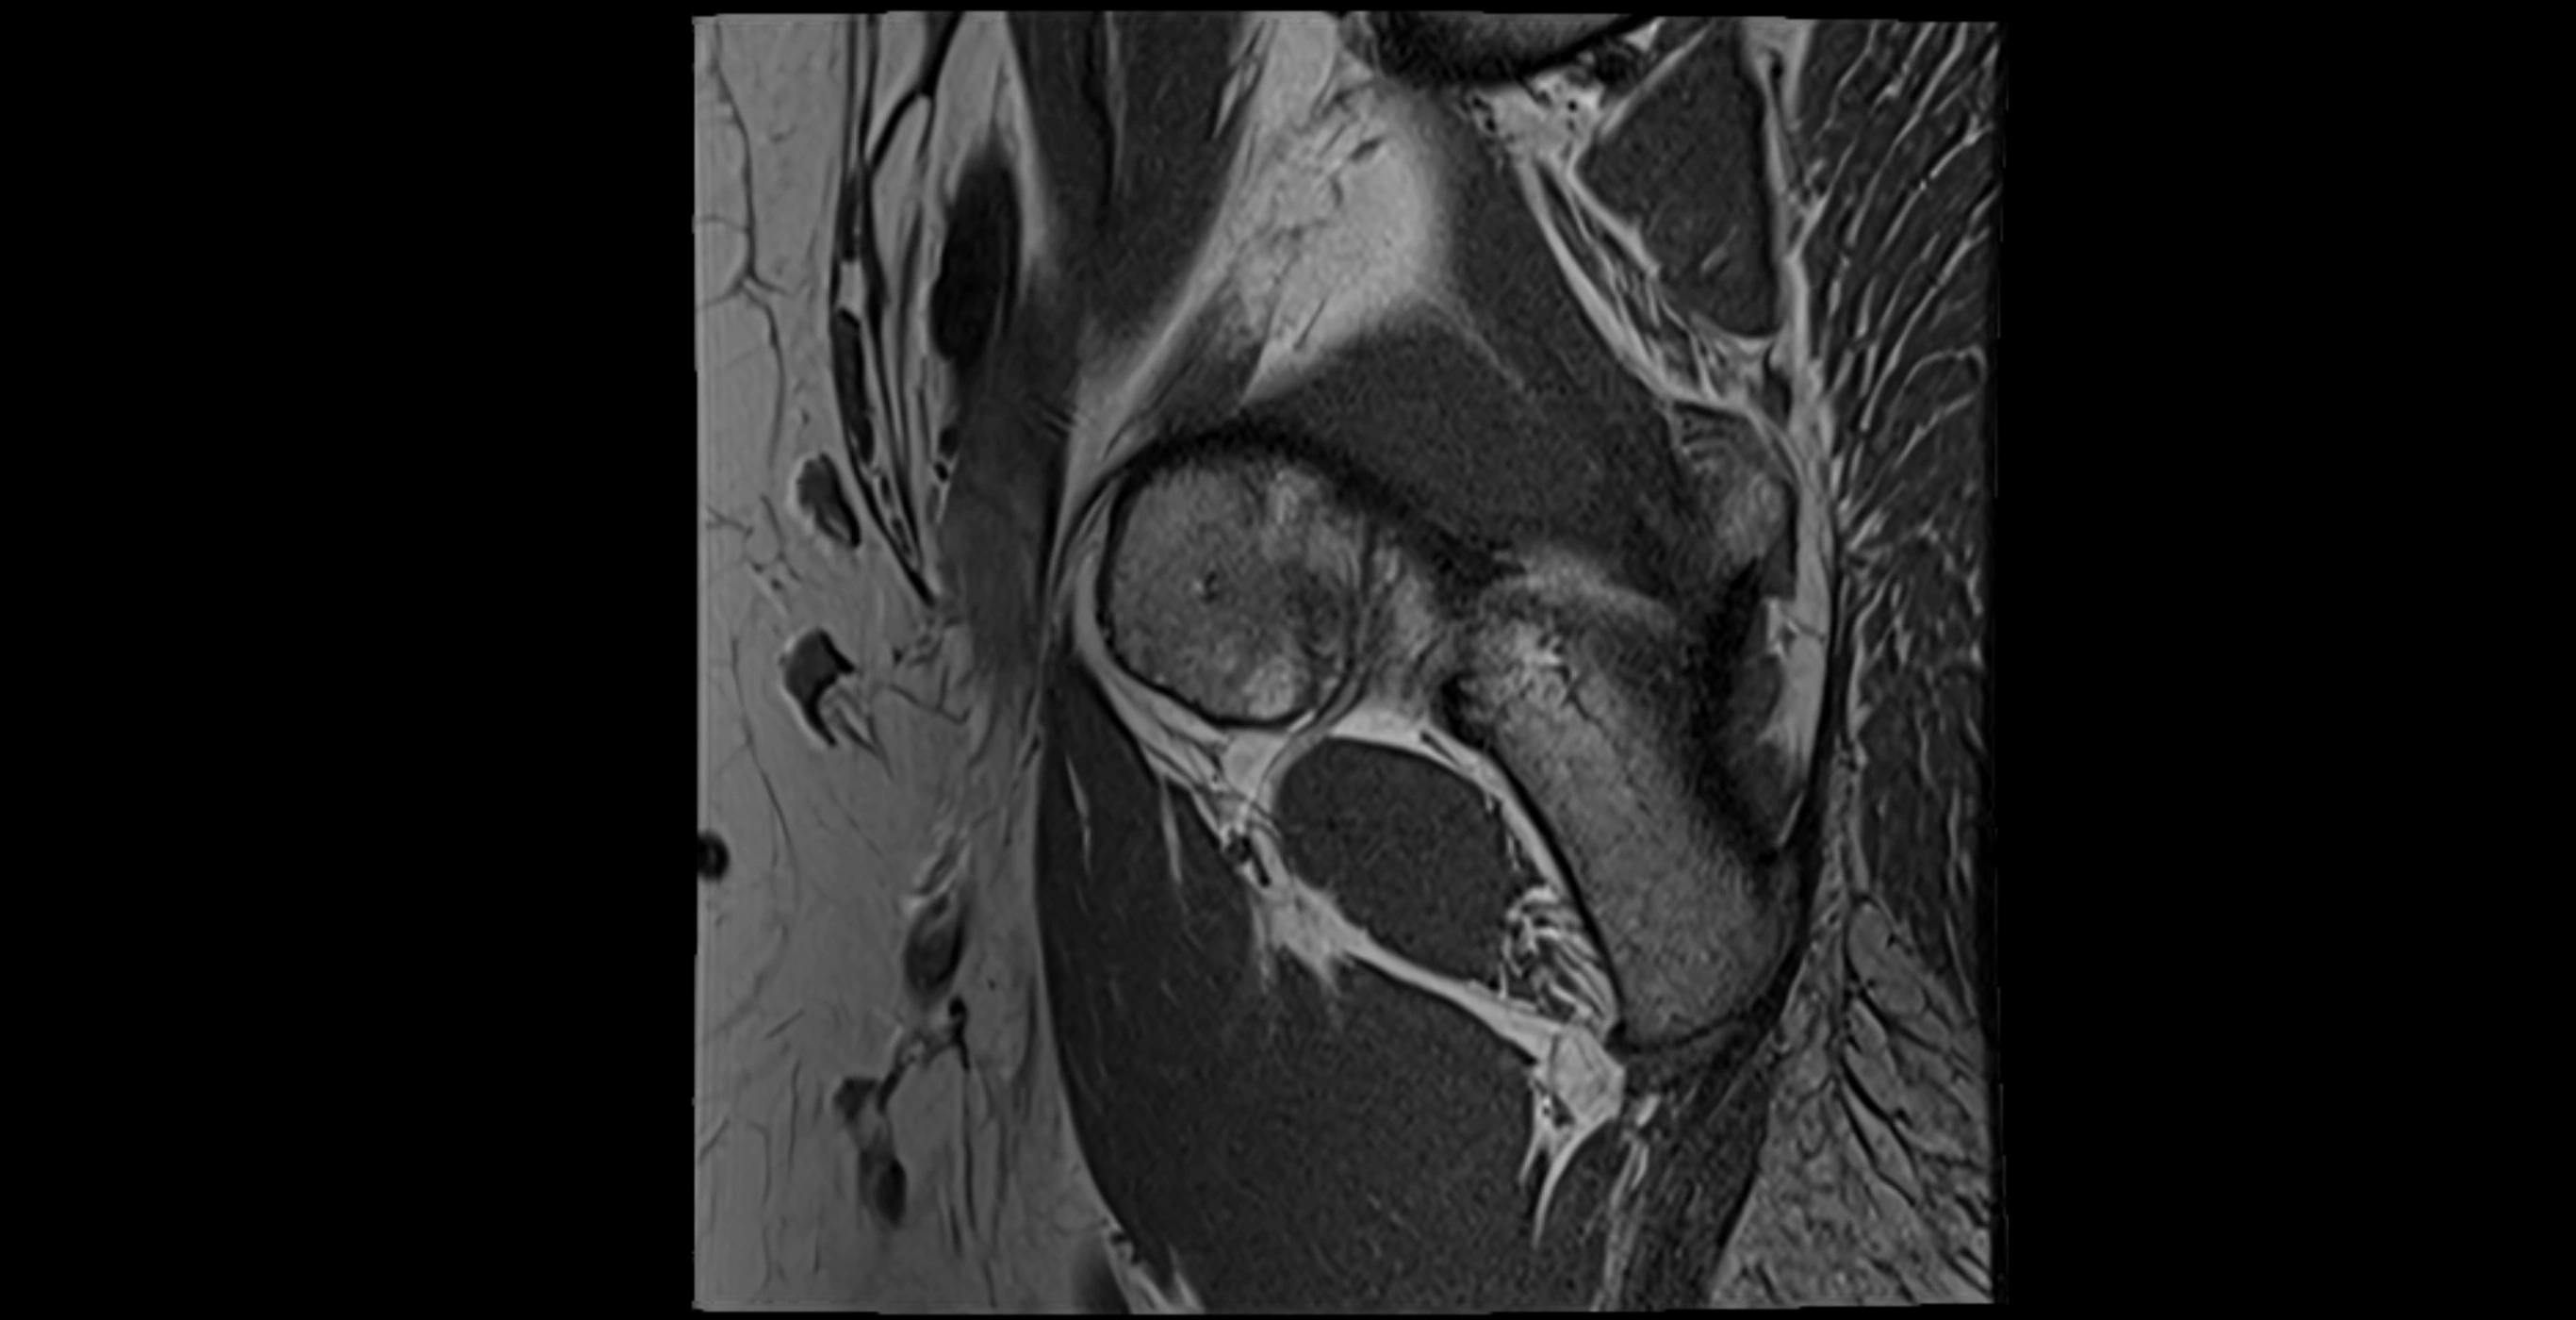

MRI image

image

MRI Appearance

T1-weighted images:

• Labrum: low signal intensity (dark)

• Surrounded by intermediate signal joint fluid (bright on arthrogram)

• Tears: linear or focal areas of intermediate-to-high signal interrupting labral continuity

T2-weighted images:

• Joint fluid: bright, making labral tears visible as fluid extending into or around labrum

• Degeneration: may show areas of increased signal within labrum